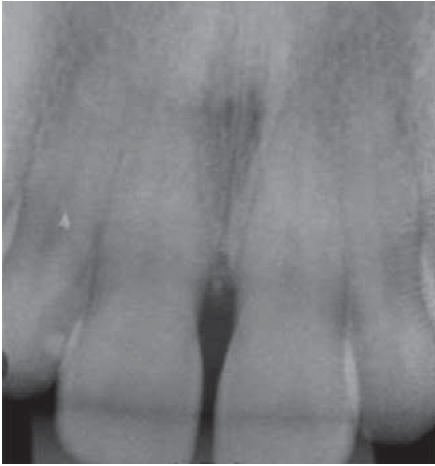

Al examen radiográfico se observó alteración de la cresta ósea entre las piezas 1.1 y 2.1 (Figura 10).